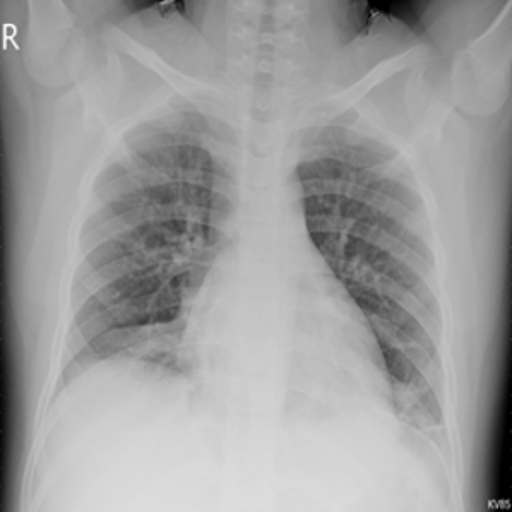

4.1 Qualitative Evaluation of Healthy Counterpart Generation

Example images from the disease COVID-19 Radiography Database and their generative healthy counterparts are given in figure 2. The images on the far left are instances of the lung opacity class from the real images in the dataset. The images in the middle column are examples of the generated healthy counterfactuals obtained via latent space diffusion, with RadBERT-guided textual-conditioning via a conditional prompt “normal chest x-ray”. A total of 75 diffusion inference steps are used with image conditioning strength=0.85 and guidance scale=7.5. (The former indicates the level of constraint on changes to the original input image and the latter is the weight given to the textual encoder conditioning in the generation of the image, ranging over [0,1] and [0,9], respectively).

Side-by-side inspection of the generated healthy counterfactuals (as per fig. 2) suggests that, as required, only minimal perturbation is made to the original image with respect to healthy pixels -i.e. localized image sites without structural medical defects. (In the top row, the medical structural defect in the original image is due to a lung opacity, and characterized via a relatively complex interaction between the imaging modality and subject manifesting as ‘gaps’ in the corresponding portions of the lung scan). The healthy/non-healthy discrepancy maps in all of these cases are obtained via masked subtraction of the original image from the generated image (the ground truth segmentation masks correspond to the broad area of interest –i.e. the complete lung). The generated healthy tissue is thus a subset of the mask and is shown in the final column of fig. 2 for the respective cases.

In the context of a VANT-GAN[20]-based approach, this highlighted material constitutes the diagnostic counterfactual visual attribution, i.e. the selection of material relevant to the diagnosis of the unhealthy condition. Healthy counterfactual generation was performed for the complete datasets in the three unhealthy classes, i.e Lung opacity, Viral Pneumonia and COVID, examples of which are given in fig. 3 for the three classes (all of the generated healthy counterfactuals from this experiment can be found on https://huggingface.co/ammaradeel/diffusionVA). Visual inspection indicates that the generated counterfactuals are, in general, visually plausible with minimal perturbation made to the unhealthy image overall. Moreover, the healthy counterpart generation does not appear to unnecessarily affect aspects of the images unrelated to the medical condition, the model selectively making changes to the unhealthy regions in a structurally plausible manner, e.g. generating missing portions of the lung without generating extraneous lung material where it would be expected to normally exist (e.g. in the abdominal cavity).